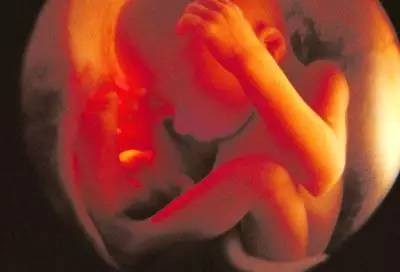

第五个月

胎宝宝身长20-25cm,体重250-300g。皮肤呈暗红色,出现胎脂,此时的宝宝已经长出细茸的头发了。胎宝宝已经开始出现吞咽和排尿了。这个月开始胎儿运动明显增加,10%~30%时间胎动活跃,大部分孕妈已经可以感觉到胎动了。